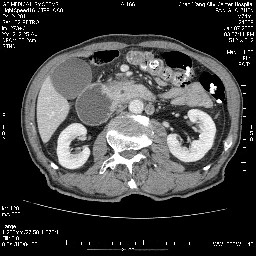

病变主要位于钩突(癌)。如是壶腹部,肝内外胆管扩张明显。

病变考虑为钩突癌。

十二指肠降段扩张,水平段狭窄成鼠尾状,肠壁明显增厚,胰腺勾突增大成不均匀强化,其内可见低密度区,胆囊增大,1十二指肠水平段腺癌侵犯胰腺勾突可能大,2胰腺癌侵犯十二指肠(只有胆囊增大没有肝内外胆管扩张不好解释)代除外.

十二指肠降段扩张,水平段狭窄成鼠尾状,肠壁明显增厚,胰腺勾突增大成不均匀强化,其内可见低密度区,胆囊增大,1十二指肠水平段腺癌侵犯胰腺勾突可能大,2胰腺癌侵犯十二指肠 。

今日手术结果:胰腺钩突癌侵犯十二直肠,腹腔淋巴结转移.